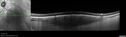

BRAO - plaques in vessels - GIF video of FA3 views78 year old female with vision loss for 1 week and old macular scar. Images show BRAO with plaques and FA shows occlusion.Oct 13, 2025